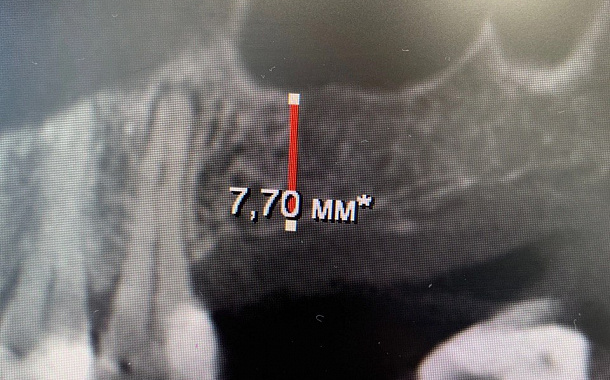

Применение Indiba после стоматологических процедур, таких как удаление зубов, костная пластика и имплантация, обеспечивает ряд значительных преимуществ:

- Улучшение приживаемости имплантатов: усиление кровоснабжения в области имплантации способствует лучшей интеграции имплантата с костной тканью.